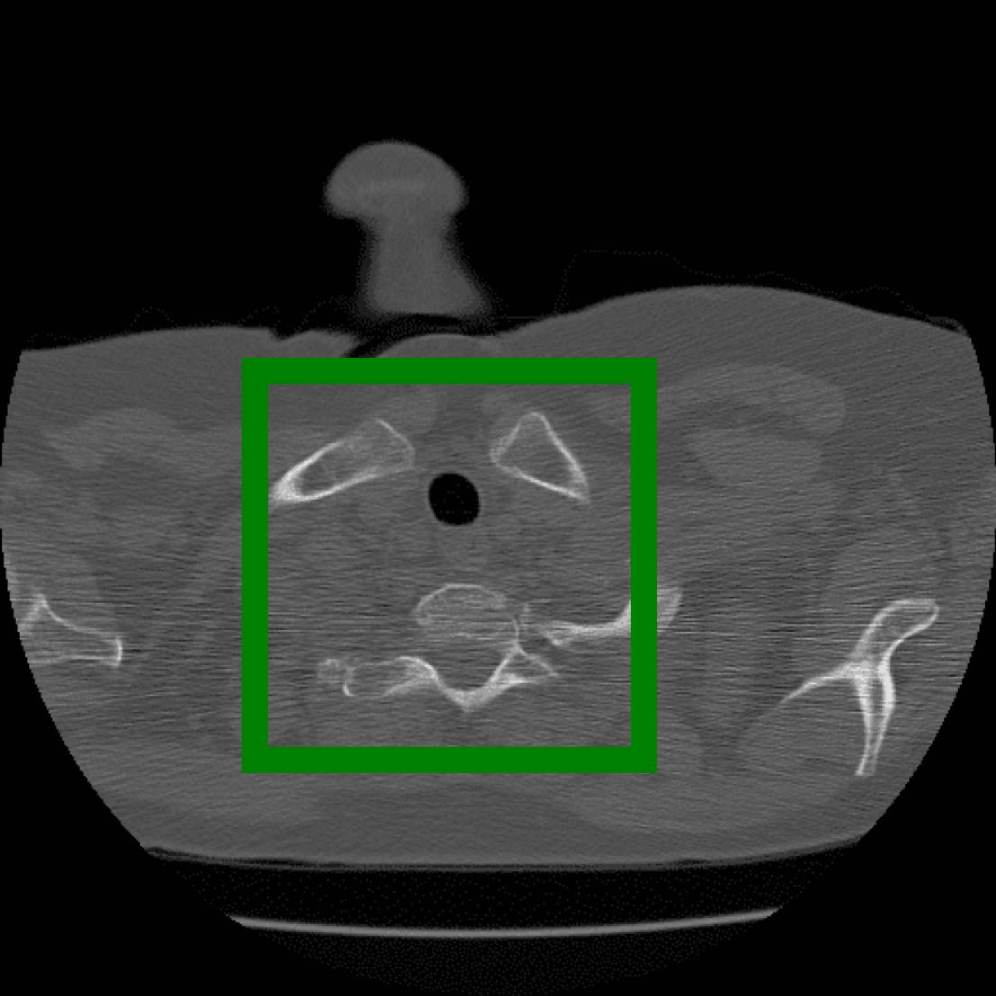

Figure 10: The visual comparison of different compression methods on a CT Heart Segmentation image.

Figure 11: Zoomed-in view of the highlighted region in Figure 10.

Figure 12: The visual comparison of different compression methods on another CT Heart Segmentation image.

Figure 13: Zoomed-in view of the highlighted region in Figure 12.

IV-B3 Visual Comparison

Figures 7 and 8 present representative examples from the CIL dataset and their zoomed-in regions, respectively. For the CT Heart Segmentation dataset, Figures 10 and 12 illustrate typical reconstruction results, while Figures 11 and 13 further enlarge local regions to compare structural details. Across both datasets, COLI preserves fine structures and global continuity well even at relatively low bpp. Specifically, on the CIL dataset, COLI attains the lowest bitrate among INR-based methods while still maintaining clear texture details. On the CT Heart dataset, COLI also operates at a low bpp within the INR family and delivers superior visual quality with improved detail fidelity and smoother structural presentation. The zoomed-in regions show fewer blocking artifacts and smoother transitions, making COLI especially suitable for large images and medical images. These visual results validate that INR-based compression can achieve efficient storage with reliable perceptual consistency, offering practical advantages for real-world large-scale image processing.